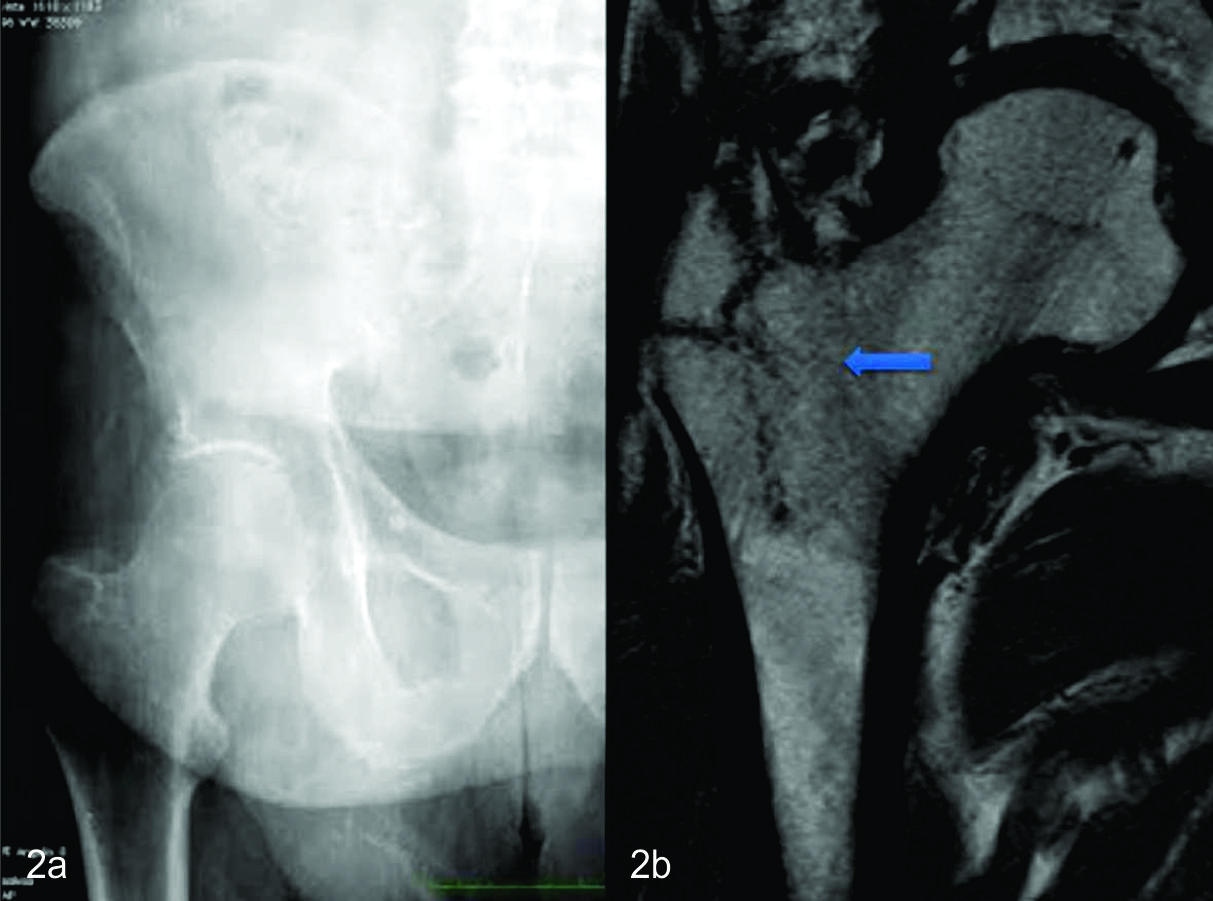

Figura 2

88 años, sexo masculino.

a) Radiografía de pelvis frente, sin evidencia de fracturas. Esta paciente es obesa, y se observa el manto de panículo adiposo que se interpone en la proyección radiográfica. b) RM de pelvis coronal. Secuencia TSET1. Se observa fractura en trocánter mayor derecho con extensión intertrocantérica (flecha), hipointensa en T1 sin desplazamiento signficativo de fragmentos óseos.